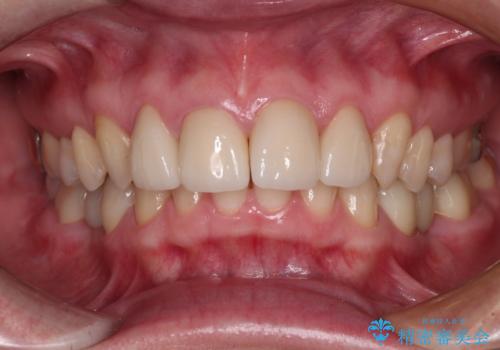

- 下顎前歯が抜けそうとのことで来院された患者様です。

初診の状態ではすぐにでも抜けそうな状態で、インプラントによる補綴治療を行うこととしました。

インプラント治療に際し、前歯の叢生に対する矯正治療を提案したところ、興味を持たれたので、インビザライン・ライトによる矯正治療を行うこととしました。

抜歯後にスペースができると恥ずかしいため、抜歯した歯を接着剤で固定した上で矯正治療を行い、その後インプラントやオールセラミッククラウンの装着を行うこととしました。